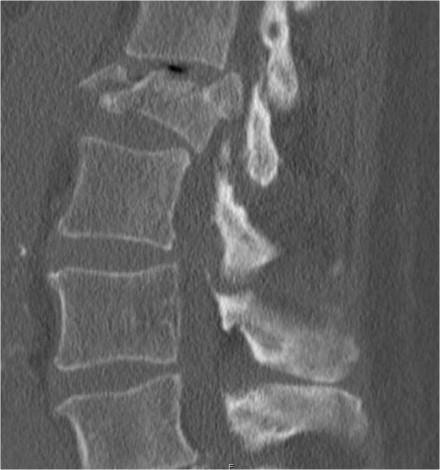

The findings are:

- Morphology: Translation - 3 points

- PLC: always disrupted in translation - 3 points

- TLICS: 6 points